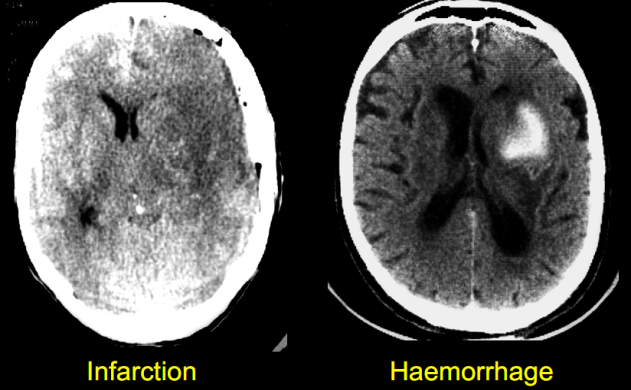

Đột quỵ được chia thành hai thể: nhồi máu não hoặc chảy máu não.

Đúng hơn có thể chia thành 3 thể (theo ICD 10 ở trên) là xuất huyết dưới nhện, xuất huyết trong não và nhồi máu não, bởi vì biểu hiện lâm sàng và cận lâm sàng của hai thể xuất huyết có nhiều khác biệt.

Loại tai biến này chiếm 80%.

Loại tai biến này chiếm 20%, trong đó:

Chảy máu não thường có biểu hiện rất cấp tính, rầm rộ, toàn thể, có thể gây rối loạn ý thức nhanh, hôn mê và tử vong do đó cần phải xác định sớm bằng xét nghiệm hình ảnh học (CT cấp cứu).